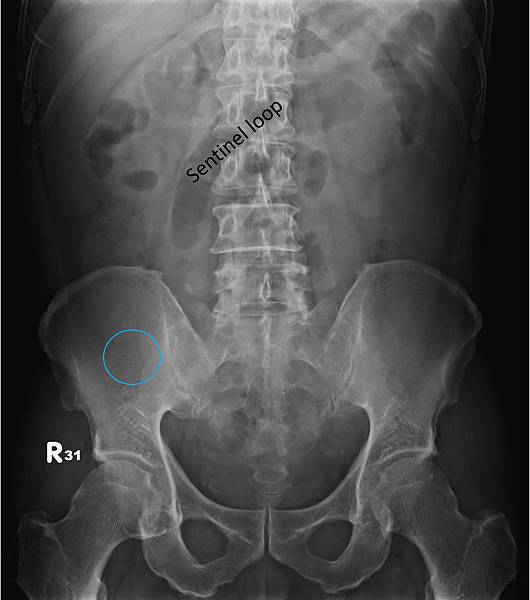

KUB看不出她的病有多嚴重:

CXR才是診斷的經典:

右側橫膈下方有經典的Free air,

是胃/十二指腸或小腸或大腸破了!一個胃或腸的小破洞,電腦斷層無法判定哪兒破了,一般外科開下去發現是遠端降結腸(Distal descending colon)破了一個洞(0.5 cm),於是找直腸外科繼續完成手術。

她的早期診斷是結腸憩室炎,拖了十幾天破掉,如果一週前就去看病,診斷出來用抗生素治療,她就不必開刀先做人工肛門,然後再開一次刀把大腸接回去,住院折騰兩個多月。新冠疫情下,即使是有錢人生病也會忍著看會不會自己好起來。wleemc 發表在 痞客邦 留言(9) 人氣(612)